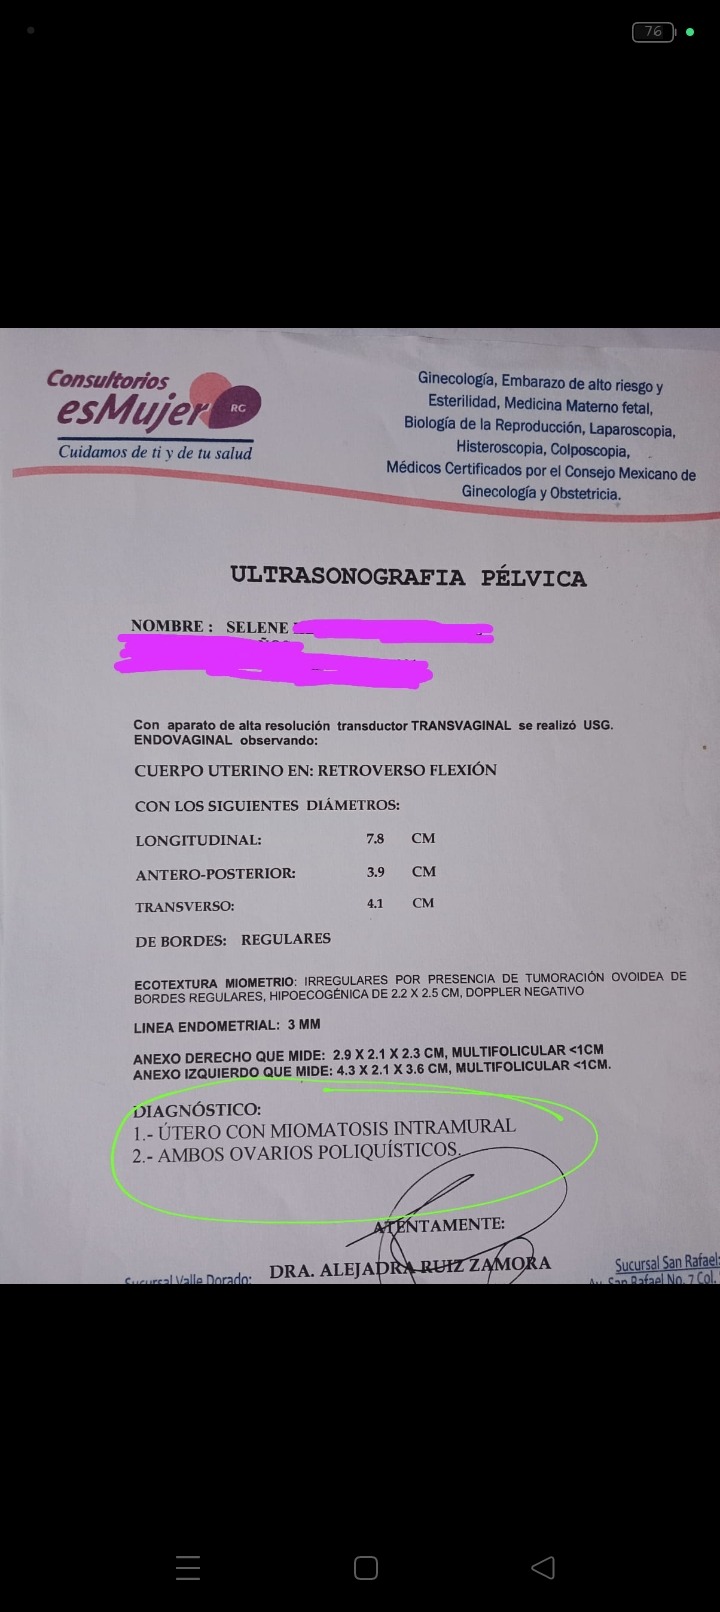

Tengo 30 años de edad , y desde los 21 años padezco de esta enfermedad conocida como: Síndrome de Ovario poliquístico, miomas, quistes y también en la matriz . Cómo se podrán imaginar vivir con esto no es fácil ya que es doloroso y se vuelve aún peor al pasar de los años.

Después de unos largos 4 años logre ahorrar un poco para iniciar mi tratamiento de nuevo. Tuve mi cita este 24 de octubre, donde mi doctora me reviso y urgentemente ese mismo día me realizo un estudio, el cual me comentó que ya no puedo dejar seguir dejando más tiempo sin atenderme. Así que me mandó a realizar más estudios, y también a realizar una biopsia.